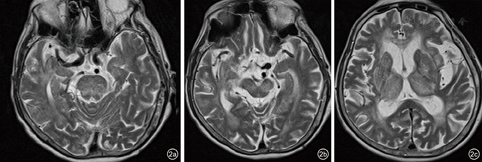

患者,女性,91岁,因"突发反应迟钝伴左侧上下肢无力1 d"入院。患者16 h前出现神智模糊,反应迟钝,活动减少,不愿进食,无呕吐,无二便失禁,无肢体抽搐;2 h前意识障碍加重,伴有头痛、呕吐,遂于安徽医科大学附属合肥医院急诊科就诊,急诊头颅CT提示左侧小脑出血(图1),收入神经内科。患者既往高血压病史多年,不规则服用降压药物,平时监测较少。查体:体温36.8 ℃,血压230/134 mmHg(1 mmHg=0.133 kPa),双肺呼吸音粗,未闻及干湿性啰音,心率100次/min,律齐,偶闻及期前收缩,未闻及杂音。神经系统检查:嗜睡状,问之无应答,额纹对称,双侧瞳孔直径2.5 mm,对光反射存在,双眼右向凝视,左侧上下肢肌张力低,肌力Ⅱ级,右侧上下肢肌力V-级,右侧上下肢肌张力正常,双侧巴氏征未引出。实验室检查:红细胞计数为3.99×1012/L,中性粒细胞计数为15.36×109/L,中性粒细胞百分数83.21%,白细胞计数为18.48×109/L,尿素氮25.50 mmol/L,肌酐382.0 mmol/L,血钾6.15 mmol/L。心电图提示窦性心动过速。头颅CT提示左侧小脑半球出血,双侧侧脑室旁、丘脑、脑桥大片状低密度灶。入院后即刻予以吸氧、心电监护、促醒、脑保护、抑酸护胃、补液支持、脱水降颅压、调节电解质紊乱等治疗,并静脉滴注硝酸甘油以0.25 mg/h调节血压。入院后约14 h患者出现高热达39.9 ℃、呼吸道分泌物明显,意识障碍进一步加重呈中-深度昏迷,考虑肺炎,予以抗炎、化痰、补液、促醒等处理,持续静脉使用硝酸甘油加量至1 mg/h,血压仍持续达(180~200)/(110~120)mmHg,降压治疗效果差,血尿素氮、肌酐进一步恶化。肺部CT提示慢性支气管炎、肺气肿、右肺炎;头颅MR提示双侧侧脑室旁、丘脑、双侧桥脑、中脑广泛T1WI低、等信号,T2WI及FLAIR像呈高信号,弥散加权成像呈低、等信号,表观扩散系数图无信号(图2、图3)。患者于入院后46 h神志转清,血压(120~130)/(80~90)mmHg,左侧肢体肌力恢复至Ⅳ级,要求下床小便,停用硝酸甘油,加用口服非洛地平缓释片5 mg,2次/d,联合厄贝沙坦氢氯噻嗪片1片,1次/d调节血压,余治疗继续予以原方案。半个月后复查头颅MR除小脑出血病灶存留,其余异常信号完全消失(图4)。入院25 d后患者病情稳定,血压120/70 mmHg,可自主进食、正常交流及下床自行活动,予以出院。随访1个月病情无反复。

RPLS病灶主要累及大脑半球后部,如顶叶、枕叶、额颞叶、小脑、基底节及脑干等。中央变异型RPLS可伴有丘脑或脑室旁白质受累[6,9]。本例患者是双侧对称的脑干、丘脑、脑室旁受累,该类型常与高血压密切相关,及时诊断及治疗后大多临床转归较好[1,2,10]。